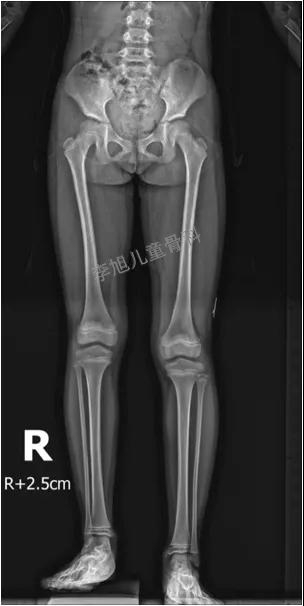

而我们要求的片子必须是这样子滴。除了单纯的骨盆正位片外,我们要求孩子必须还有一张站立位的下肢全长片。才可以判断,孩子有没有原发的或继发的双下肢不等长。而且,对于髋关节是否还存在某种程度的不稳定,也只有站立位的片子才能够真正表现出来。